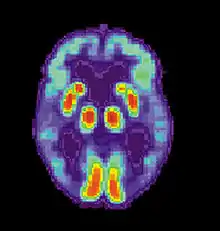

پت اسکن از بیماری الزایمر